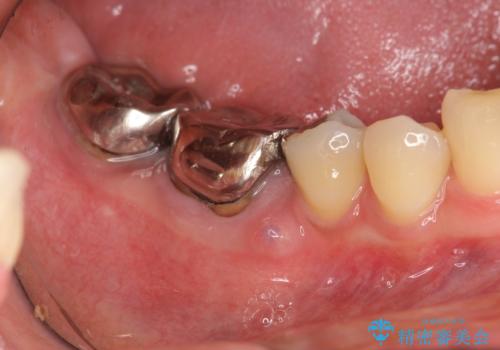

- 他院で根管治療を受け銀歯をかぶせるところまで行ったが、直後より腫れ・痛みが引かず当院へ相談、来院されました。

X線写真検査より根管充填の行われていない根管、視診より歯肉からの排膿路を認め、急性根尖性歯周炎の治療として根管再治療を計画します。

治療途中、マイクロスコープでも根管が追えないほど狭く細くなった根管へと変性しており根管の拡大形成が難しい状況でした。

CTを撮影し少しづつ丁寧に根管を探索することで無事根管再治療を行い、症状がなくなりました。